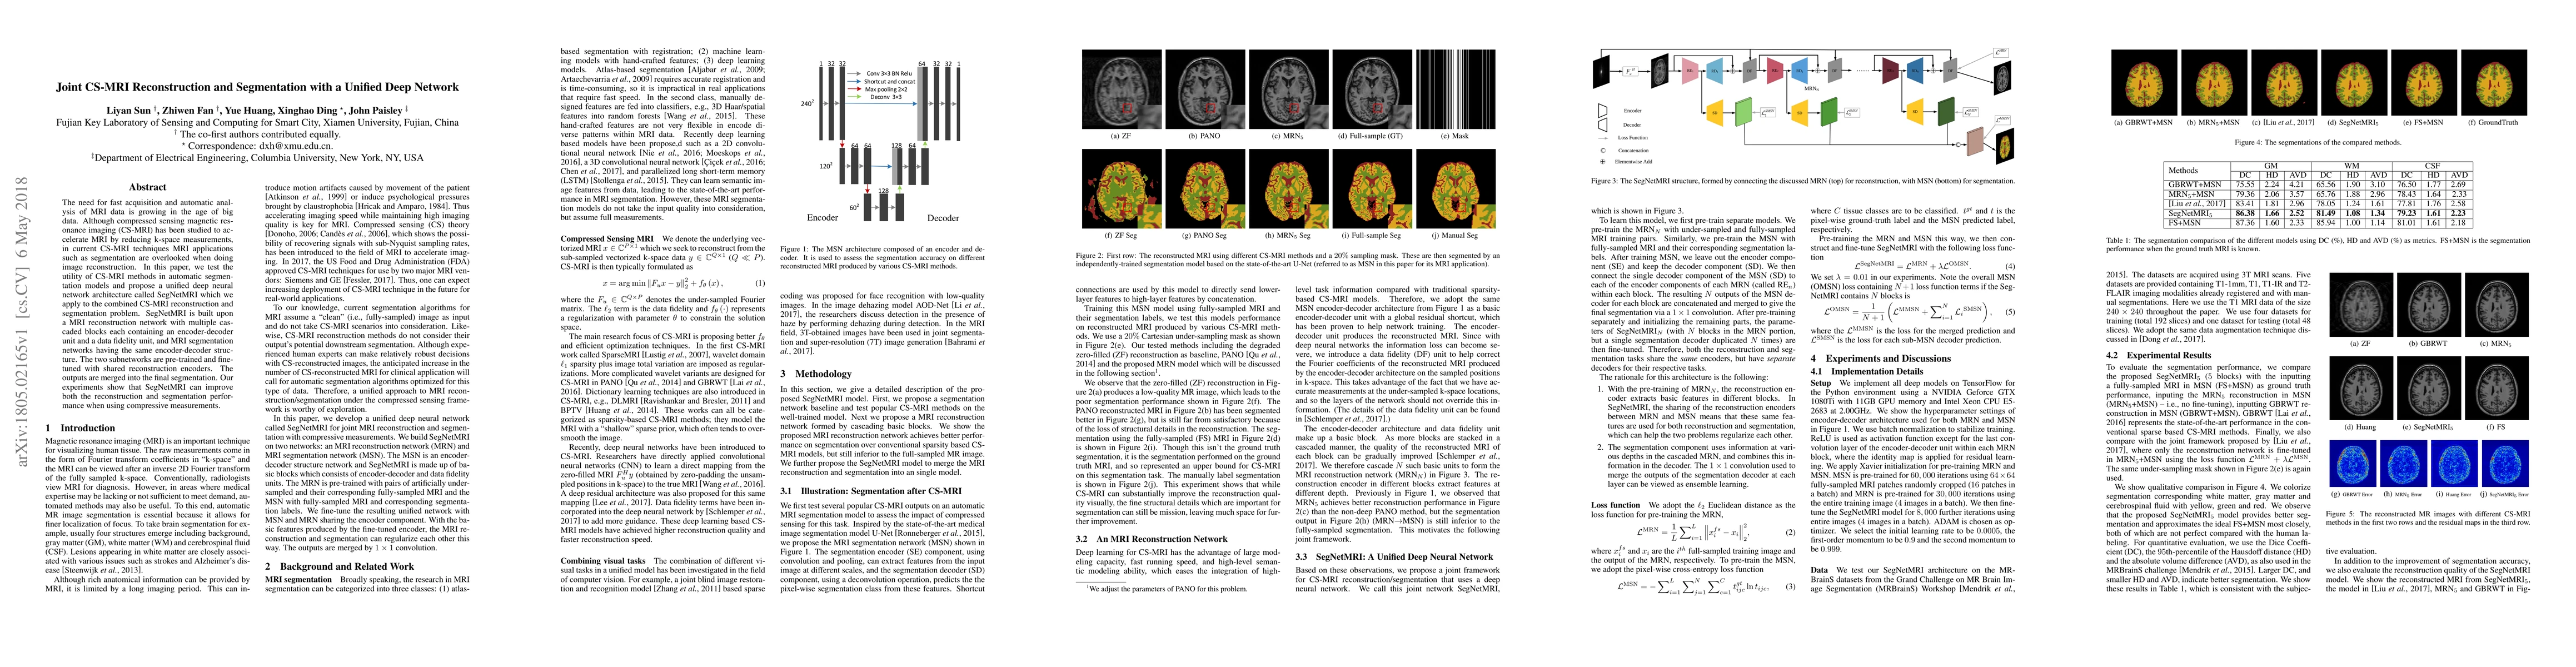

The need for fast acquisition and automatic analysis of MRI data is growing in the age of big data. Although compressed sensing magnetic resonance imaging (CS-MRI) has been studied to accelerate MRI by reducing k-space measurements, in current CS-MRI techniques MRI applications such as segmentation are overlooked when doing image reconstruction. In this paper, we test the utility of CS-MRI methods in automatic segmentation models and propose a unified deep neural network architecture called SegNetMRI which we apply to the combined CS-MRI reconstruction and segmentation problem. SegNetMRI is built upon a MRI reconstruction network with multiple cascaded blocks each containing an encoder-decoder unit and a data fidelity unit, and MRI segmentation networks having the same encoder-decoder structure. The two subnetworks are pre-trained and fine-tuned with shared reconstruction encoders. The outputs are merged into the final segmentation. Our experiments show that SegNetMRI can improve both the reconstruction and segmentation performance when using compressive measurements.